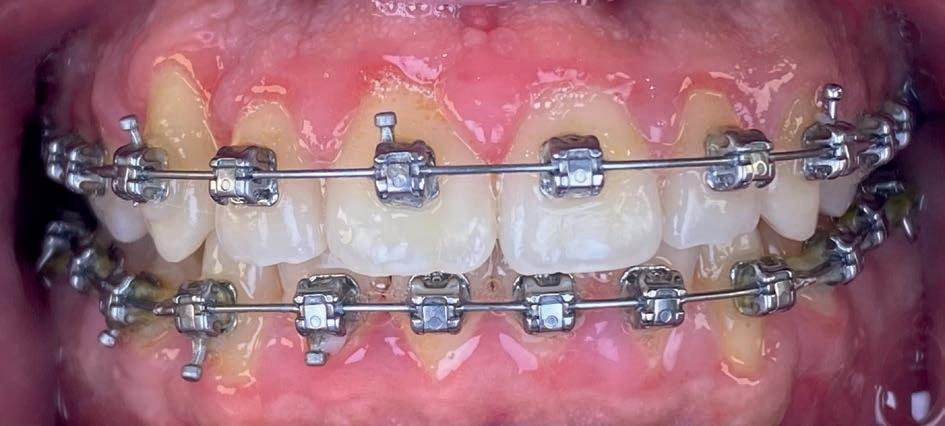

Casus in Proces

Patiënt Sonnie presenteerde zich met ernstig ruimtegebrek ter hoogte van de 13 en 44 en een kruisbeet aan de zijde van de 15 en 14. De 13 was ectostematisch gepositioneerd, waardoor extractie aanvankelijk als mogelijke behandeloptie werd overwogen.

Door een combinatie van verbreding en het inzetten van een D-gainer wordt de benodigde ruimte gecreeerd om alle elementen correct in de tandboog te positioneren, waardoor extracties kunnen worden vermeden. De behandeling zal binnen twee jaar worden afgerond; het eindresultaat wordt gedeeld in editie 2 van ons magazine.

Start behandeling

Midden behandeling

Laatste fase